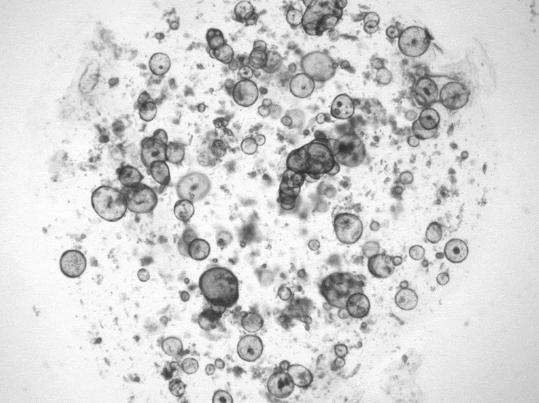

泪腺类器官产生类似眼泪的液体(红)。图片来源:Yorick Post / 荷兰Hubrecht研究所

“哭泣”的类器官因泪水而膨胀。图片来源:MarieBannier-Hélaou?t/荷兰Hubrecht研究所